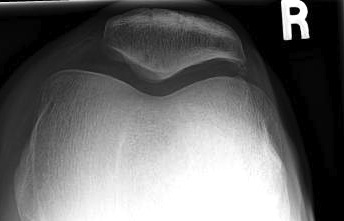

Patellofemoral view

1. Skyline view

Technique

- 45o

- shoot throught film

Look for

- OCD

- bony avulsion MPFL

3. Merchant view / patella subluxation

- 40o flexion, beam from top

- patella should be well engaged

- central ridge should lie at or medial to bisector of the trochlea groove

Congruence angle

- draw sulcus angle

- bisector of sulcus angle

- line to central ridge of patella

- should be - 10o (i.e. medial)

- lateral direction is positive

Normal

Subluxed

4. Trochlea dysplasia

Sulcus angle

- > 140o flattened